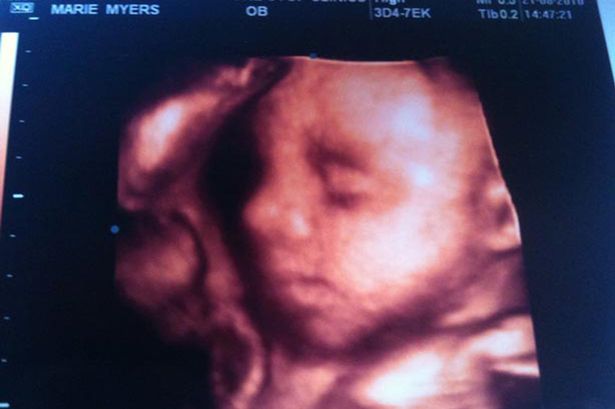

Η Μαρί τον καθησύχασε, γνωρίζοντας πόσο κουρασμένος ήταν από την άνιση μάχη με την επάρατη νόσο. Του ζήτησε μόνο να φωνάξουν τους γονείς τους ώστε να τον αποχαιρετήσουν για τελευταία φορά. Έτσι γονείς και αδέλφια έσπευσαν να του πουν αντίο. Όταν έμειναν μόνοι, ο Μαρκ, είδε τον υπέρηχο της κόρης του, έκλεισε τα μάτια του και γύρισε πλευρό, αφήνοντας την τελευταία του πνοή.